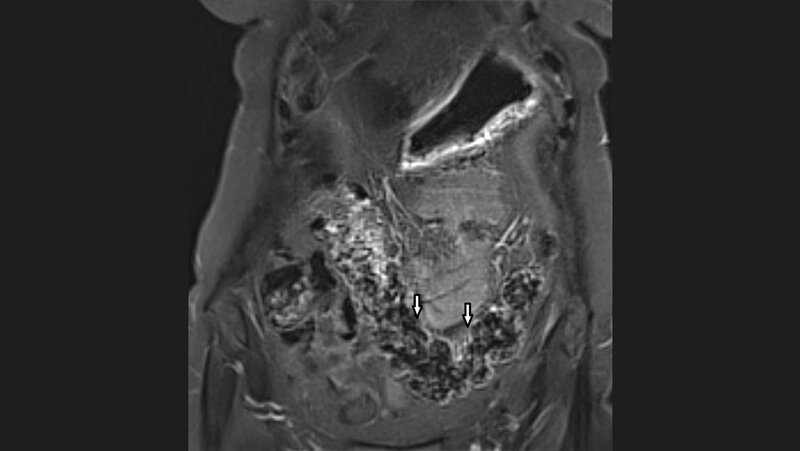

Das Dolichokolon ist eine angeborene Variante des Dickdarms, charakterisiert durch eine Verlängerung und Dilatation, insbesondere des Sigmoids. Es kann eine Symptomtrias mit chronischen abdominellen Schmerzen, Obstipation und Blähungen präsentieren.

Dolichocolon is an inborn anatomic variant, characterized by elongation and also by dilatation of the colon, especially the sigmoid. It can present with a triad of chronic abdominal pain, constipation and bloating.